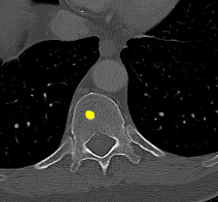

Figure 2: Qualitative results of bone lesion detection. Each column shows a cropped slice with the top row displaying ground-truth (green) and the bottom row showing nnUNet predictions (yellow). (a) shows a TP osteolytic lesion; (b) shows the prediction of a real osteoblastic lesion that was not prospectively marked as ground-truth (before review), and after GT review, it was correctly considered as ground-truth; (c) shows an osteolytic lesion not annotated in ground-truth before review and correctly marked afterwards. A FN adjacent to it is also shown. (d) shows a rare FP on the cortex of a rib.

Results. Qualitative and quantitative results of our model are presented in Fig. 2 and Table 1 respectively. Our model achieved a precision of 96.7% and a recall of 47.3% for detection of bone lesions (lytic, blastic, and mixed). We observed that the model was very confident in its predictions as demonstrated by the vast number of actual lesion predictions (TPs) compared against the FPs. Despite the high precision, the model was not very sensitive to the detection of bone lesions due to the large number of FNs.

In this pilot work, we proposed to automatically detect bone lesions in CT volumes via a proxy segmentation task using the 3D full-resolution nnUNet model. Despite the partial and incomplete 3D annotations used to train the model, it was very precise in its predictions (96.7%). Due to the nature of the weak 3D annotations, the middle slices of the predictions provided better delineations of lesions in contrast to the adjacent slices (which were only coarse bounding boxes). These results were obtained after a thorough qualitative review of the model’s predictions. Initially, the test split also comprised of only prospectively marked lesions with other potential lesions being left unmarked. We noticed that the model captured lesions that were not originally annotated by the reading radiologist. Despite the vast majority of the predictions that were considered as FPs were, in fact, real lesions (TPs), the precision and recall languished at 25.6% and 50.2% respectively as shown in Table 1 (Before GT review). The discordance between the initial quantitative and qualitative results spurred us towards a full review of our ground-truth annotations in the test split. Post completion of the review, the recomputed metrics resulted in a significant increase in the precision of our model, which was in line with the observed qualitative results.